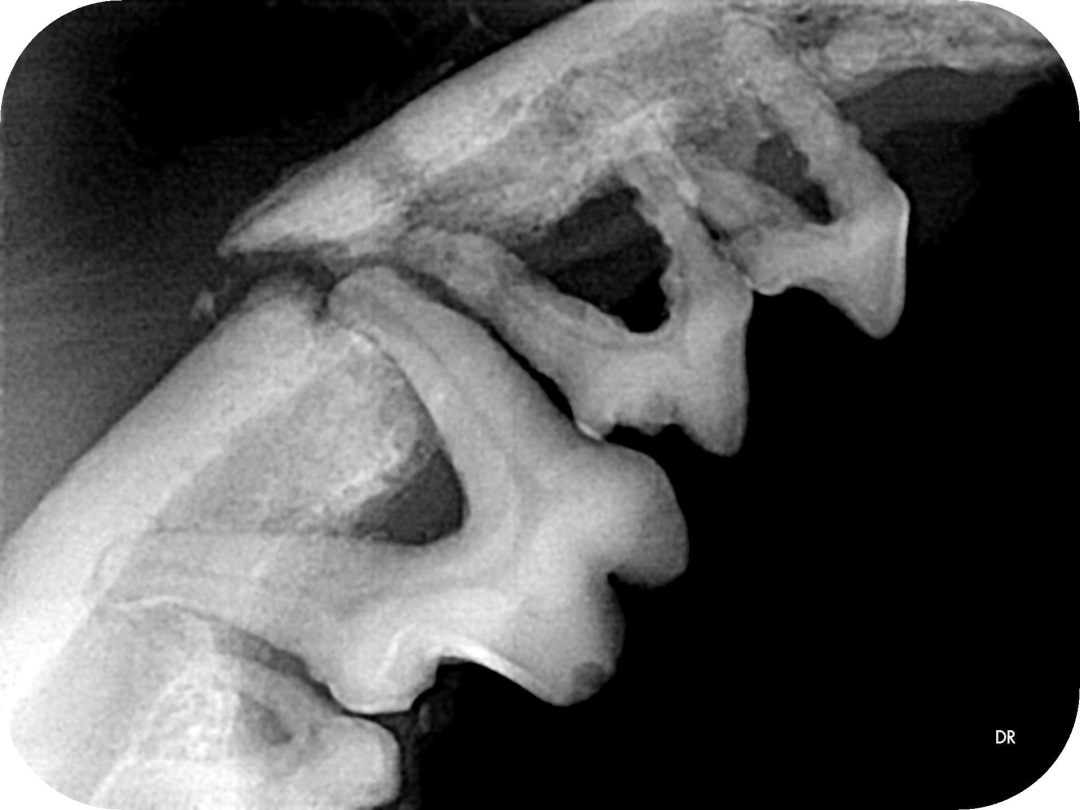

▲院内新进牙科DR设备之一

▲部分牙科DR效果展示图(可左右滑动)

什么是DR?

DR检查是影像科常用的一种检查方法,它又称为数字化X射线摄影系统,相对于传统的拍片子检查,它的辐射量更小,检查的时间更短,片子的质量也更高